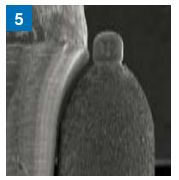

- Fotografia de Microscópio: